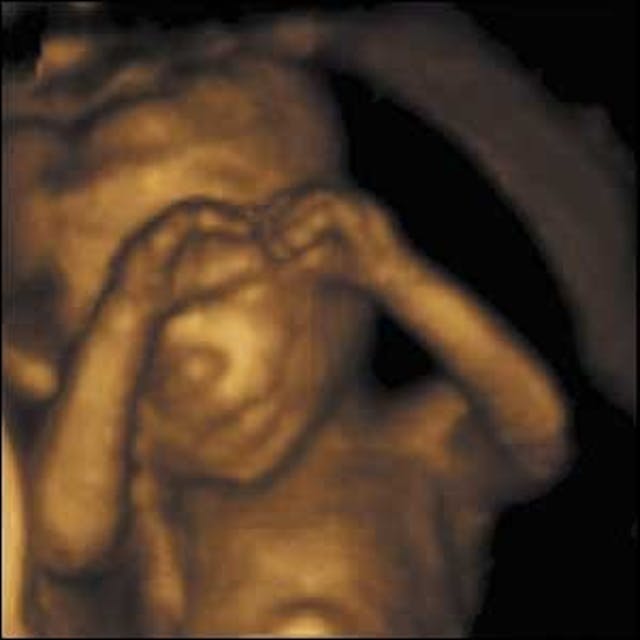

“There’s an entire generation of women who saw a sonogram as their first baby picture. There’s an increased awareness of the humanity of the baby before it is born.”

As Yoest notes, the sonogram changes everything. Even in states that have not passed more restrictive abortion laws, it is becoming harder for women to deny anything but the humanity of their preborn babies.